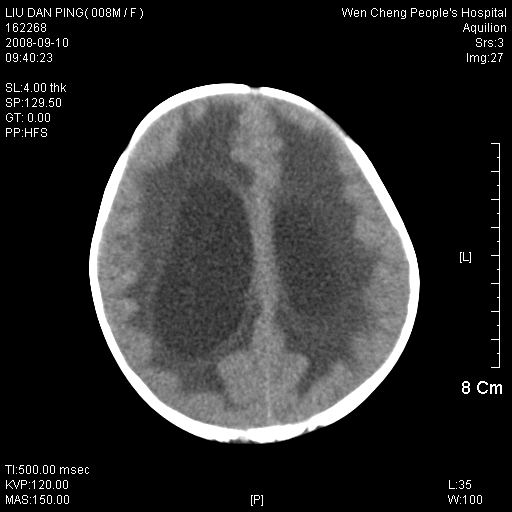

以下是引用卜一在2008-9-10 16:21:00的发言:[br]髓母细胞瘤伴梗阻性脑积水!支持![br]髓母细胞瘤特点:—般直径大于3.5cm,位于后颅凹中线之小脑蚓部。累及上蚓部的肿瘤延伸到小脑幕切迹之上,ct平扫肿瘤多呈均匀一致的高或等密度病灶,增强检查呈均匀一致的强化。病灶中有小坏死时,平扫亦可呈不均匀之混杂密度,注药后有增强。[br]

以下是引用zjzjr在2008-9-10 15:09:00的发言:[br]髓母细胞瘤伴梗阻性脑积水.